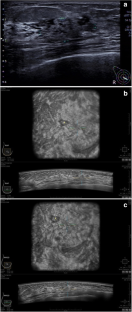

Fig. 1

Fig. 2

Fig. 3

Fig. 4